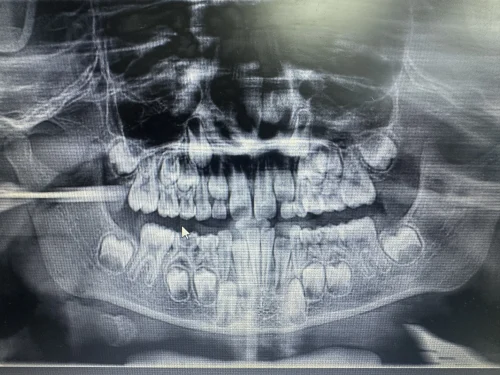

A clinical assessment presented a severely decayed primary mandibular molar #T with percussion tenderness. The radiograph of IOPAR reveals pulp involvement with furcation radiolucency, an irreversible pulpitis. The family chose Magnum Clinic because of its expertise in children's dentistry, considering that it emphasizes painless dental procedures for children

Diagnosis: Periapical in Tooth T- Irreversible Pulpitis: Which means the nerve inside the tooth is badly inflamed and the infection has reached the tip of the root. It will not heal on its own.